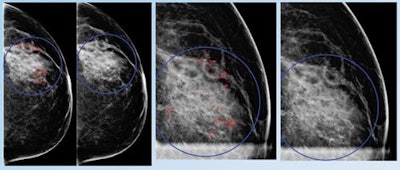

Early breast cancer was flagged by the CAD software three years prior to biopsy and showed a progressive increase in quantitative score over the three years. All images courtesy of Dr. Alyssa Watanabe.In other results, the researchers found that progressive deep-learning training continued to improve the performance of the CAD software over time for breast masses.

False positive for radiologist and true negative for qCAD. Fine linear branching and rim calcifications measuring 7 cm with regional distribution in the middle lateral region: path-proven fat necrosis.With deep-learning training, the CAD software can recognize and eliminate benign lesions, she said.